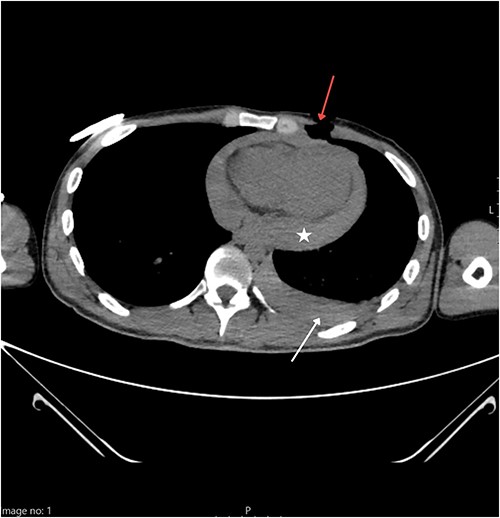

A 25-year-old Caucasian male presented to the nearest emergency department following a suicide attempt. He reported trying to commit suicide by stabbing himself with a kitchen knife which he pulled out of his chest after he realized he was not succumbing to death as fast as the pain he felt was intensifying. On admission, he was responsive with a Glasgow Coma Scale of 14, but in hemorrhagic shock with blood pressure of 80/60 mmHg and tachycardia. The patient was immediately admitted to the intensive care unit (ICU) where the initial work-up included physical examination, blood lab tests, chest X-ray, and emergency computed tomography (CT) of the thorax. Norepinephrine and blood transfusions were administered. CT imaging revealed a left pneumothorax measuring a maximum of 41 mm along with a hemothorax of 24 mm, and a hemopericardium that measured 34 mm (Fig. 1). A chest drain was placed into the left pleural cavity, and the patient was transported to the cardiac surgery department of our institution where an emergency surgical procedure was performed.

Thoracic CT showing a penetrating wound to the left pectoral area (red arrow) along with hemorrhagic pleural effusion (white arrow) and hemopericardium (star).